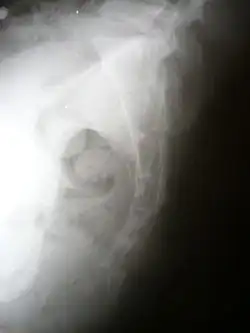

Lateral radiograph showing a fracture of the coccyx, as well as a lower lumbar fracture | |

A coccyx fracture is a fracture of the coccyx, commonly called a broken tailbone or ‘puzzle fracture.’